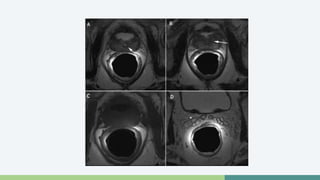

Resonancia Magnética

• Se usa cuando hay antígeno elevado y biopsia negativa

• Se puede utilizar pre o post Qx

• Se busca si hay extensión extracapsular

• Permite visualizar invasión de la vesícula seminal

• T2

T1 vs T2

Errores en el Diagnóstico

• Presencia de Sangre

• Prostatitis

• Fibrosis del Estroma

Carcinoma Prostático

Resonancia Magnética •Se usa cuando hay antígeno elevado y biopsia negativa • Se puede utilizar pre o post Qx • Se busca si hay extensión extracapsular • Permite visualizar invasión de la vesícula seminal • T2

Errores en elDiagnóstico • Presencia de Sangre • Prostatitis • Fibrosis del Estroma